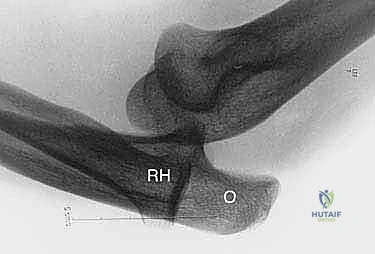

- الأشعة السينية (X-rays): لاستبعاد وجود كسور قديمة، تكلسات في الأربطة، أو تشوهات عظمية مثل الكوع الأفحج. في بعض الأحيان، قد تظهر الأشعة تكلساً صغيراً عند منشأ الرباط (علامة أوزبورن-كوتريل).

- التصوير بالرنين المغناطيسي (MRI): هو المعيار الذهبي لتصوير الأنسجة الرخوة. يستخدم الدكتور هطيف أجهزة رنين مغناطيسي عالية الدقة لتقييم مدى تمزق مركب الرباط الجانبي الوحشي (LUCL)، بالإضافة إلى فحص الغضاريف والأوتار المحيطة. في بعض الحالات المعقدة، قد يتم حقن صبغة داخل المفصل (MR Arthrogram) لزيادة دقة التشخيص.

- التصوير التألقي الحي (Fluoroscopy): فحص بالأشعة السينية الحية أثناء الحركة، يتم إجراؤه أحياناً تحت التخدير لتأكيد عدم الاستقرار قبل بدء الجراحة مباشرة.